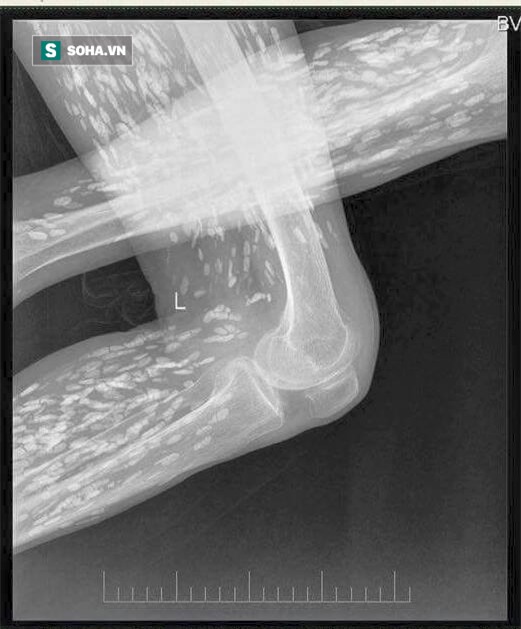

Mấy ngày nay trên mạng chia sẻ hình ảnh phim chụp Xquang của một bệnh nhân bị sán dải lợn, ấu trùng sán lợn di chuyển khắp cơ thể.

Hình ảnh đang lan truyền trên mạng xã hội được cho là của bệnh nhân đã khám và điều trị tại Bệnh viện Đa khoa trung ương Thái Nguyên. Bức ảnh được rất nhiều người chia sẻ kèm theo lời cảnh báo từ nay nên nói không với các loại thịt tái, sống, rau sống, tiết canh.

Hơn 30 năm gắn bó với chuyên ngành ký sinh trùng, bác sĩ Đề cho rằng hình ảnh này rất phổ biến, may mà ấu trùng sán lợn chưa lên não.

Bác sĩ Đề cho biết có bệnh nhân ông gặp có 300 ấu trùng sán lợn ở não và 300 ấu trùng sán lợn ẩn dưới da. Các loại ấu trùng này chụp Xquang có thể nhìn được hết.

(Ảnh: fb BS Luong Quoc Chinh)